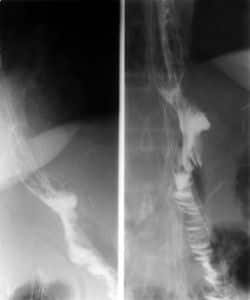

• ULCUS DUODENAL. DOS NICHOS

• ULCUS CURVATURA MENOR. ESPASMO EN LA MAYOR

• CANCER DE ESOFAGO Y GÁSTRICO